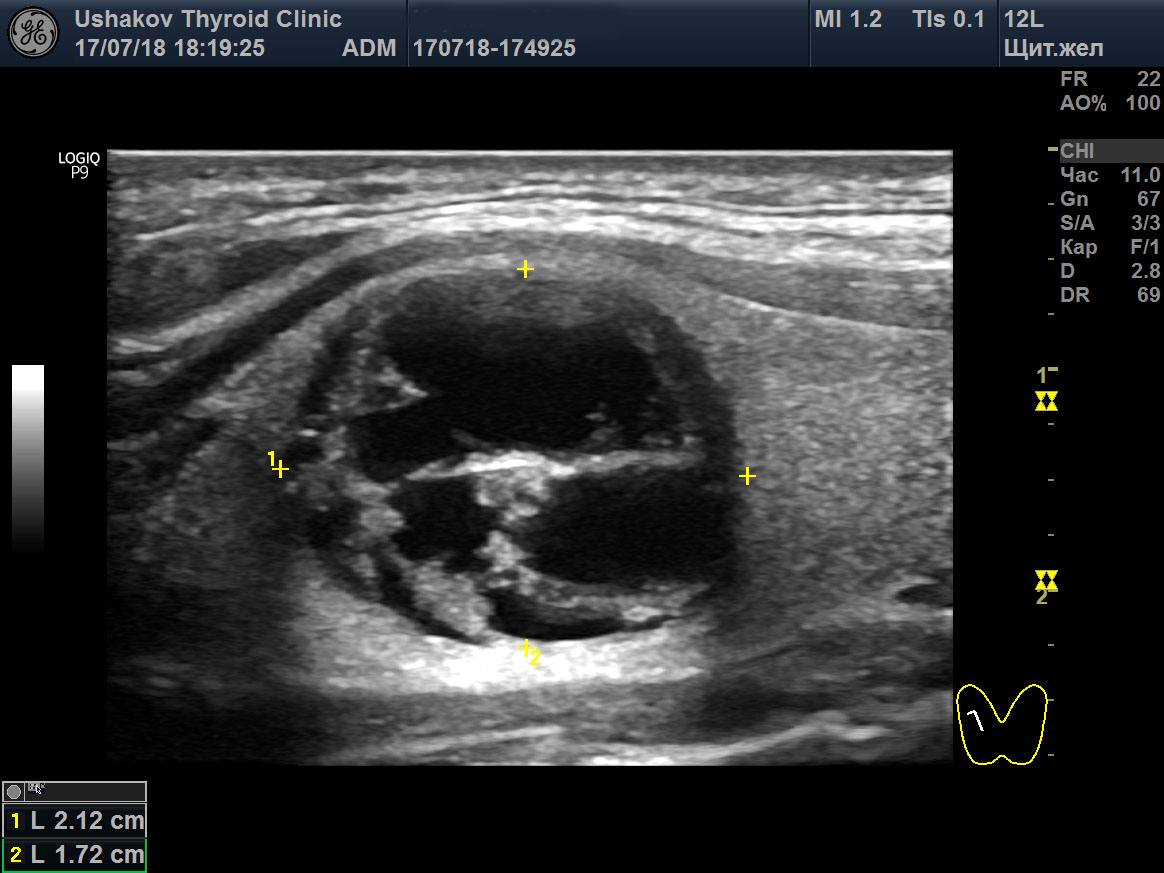

Коллоидные узлы лечение

Коллоидные узлы лечение 111 фото